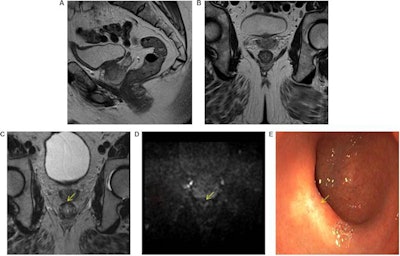

High accuracy identifying complete responders after chemoradiotherapy has been reached with the use of a three-modality approach, including digital rectal exam with endoscopy, T2-weighted MRI, and diffusion-weighted imaging. A low rectal tumor is seen on MRI (A, B). On restaging MRI eight weeks after completion of chemoradiotherapy (C), only minimal fibrosis (yellow arrow) is seen anteriorly in the rectal wall. On restaging diffusion-weighted imaging (D), there is absence of high diffusion signal (yellow arrow). Clinical assessment by endoscopy (E) reveals a white scar with telangiectasia (yellow arrow). Figure courtesy of Drs. Hester E. Haak, Monique Maas, Stefano Trebeschi, and Regina G.H. Beets-Tan and Frontiers in Oncology.Importantly, the recent decision by the European Union Commission to establish a Cancer Mission came with two key recommendations: Develop novel approaches for screening and early detection and develop a research program on early diagnostic and minimally invasive treatment technology.